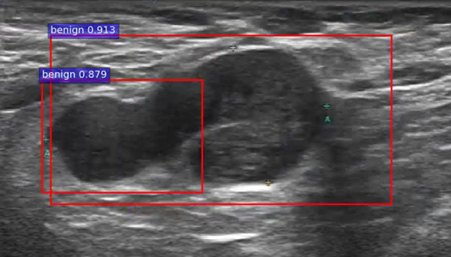

图3A-3C为乳腺超声肿瘤自动筛查效果,红框为自动标记的肿瘤,标签为良恶性。针对确诊的1200多例乳腺癌超声影像分析,准确率达85%。

图3C 自动筛查到两个病灶,良性概率为:91.3%和87.9%